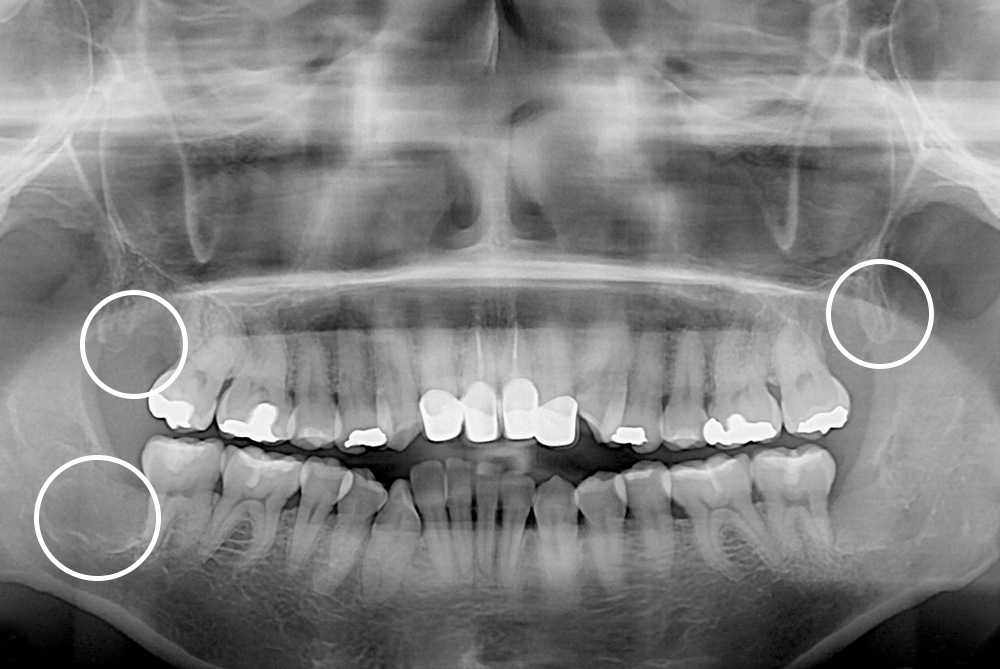

[사랑니] 매복 사랑니 발치

치료후 : 2019-12-20

세종치과는 구강악안면외과학 박사이신 원장님이 발치하는 치과입니다